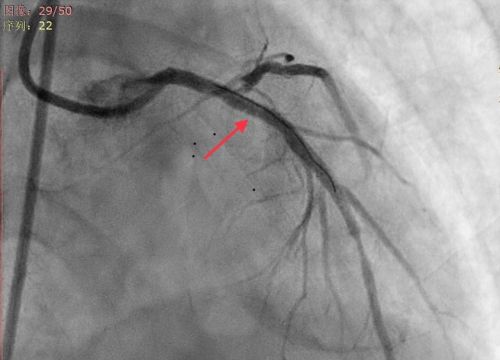

谁知,王女士刚进手术室大门便突发意识丧失,心电监护提示反复室颤。医护人员立即展开抢救,先后为她进行电除颤10余次。因患者病情来势凶猛,随时有生命危险,心内三科主任潘宏伟主任医师与张宇副主任医师、胡勇军副主任医师等立即为她施行急诊床旁主动脉球囊反搏(IABP)植入术及呼吸机辅助呼吸。随后的急诊冠脉造影证实为——冠脉左主干99%狭窄并伴有血栓,前降支完全闭塞。医生立即为她进行经皮冠状动脉介入治疗(PCI),在病变血管内放置支架,迅速打通王女士闭塞的血管。